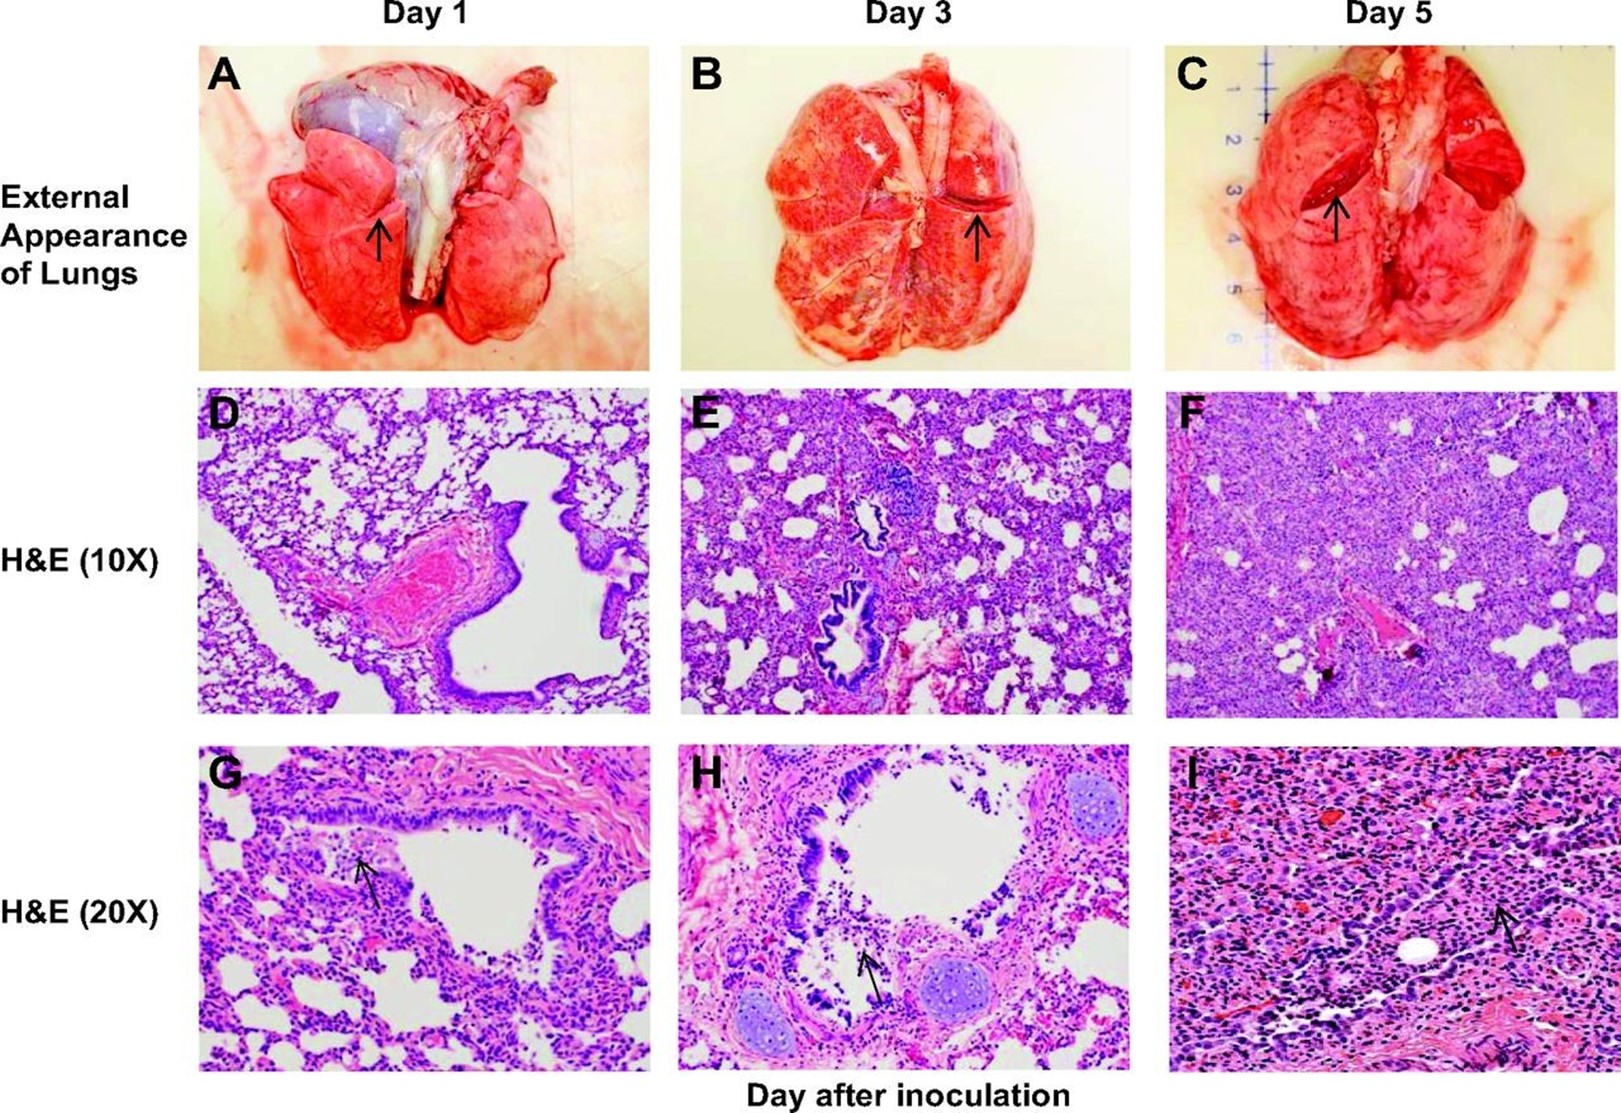

The pathological changes in the lungs of infant baboon resemble those in infant humans with RSV infection. (H&E: hematoxylin and eosin stain)

The external appearance of intact, fresh lung blocks recovered from RSV-infected animals on days 1, 3, and 5 following infection is shown in A–C. The pathophysiology of airway mucous congestion. The arrows indicate the state of the lung parenchyma in each figure. Lungs demonstrate incrementally greater vascular congestion and edema over time.

D–F demonstrate interstitial pneumonia with worsening inflammation, epithelial damage, and consolidation over time. The inflammatory infiltrate is more subtle on day 1 and found primarily in a peribronchiolar distribution with multifocal infiltration in the bronchiolar epithelium.

Progression to day 5 reveals severe thickening of the interstitium and alveolar collapse because of the worsening inflammatory infiltration. In G–I, there is progressive bronchiolar epithelial damage with sloughing, leading to partial to complete obstruction of some bronchioles with fragmented epithelium mixed with mononuclear inflammatory cells.